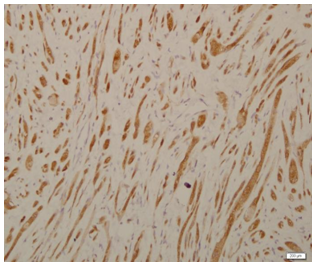

An excision biopsy specimen from a mass at elbow of 26 years old female patient was received for histopathological examination. The clinical impression was of ‘benign soft tissue tumor’. The specimen was received in 10% formalin in one container. On gross examination, it was a 1.5 x 1 x 0.5 cm well-circumscribed, grey-tan mass, without skin component. The cut surface was solid homogenous and no necrotic or hemorrhagic areas were found on it. The microscopic examination revealed a circumscribed encapsulated lesion composed of round to polygonal to spindle shaped cells with eosinophilic granular cytoplasm and centrally placed small nuclei (Figure 1 & Figure 2). Cells were arranged in intersecting bundles and mixed with fibrous connective tissue (Figure 3). The Intralesional peripheral nerve bundles surrounded by the lesional cells were seen (Figure 4). No significant mitoses or cells with cross striation, significant inflammatory infiltrate or necrosis were seen. IHC showed positive results for S100 (Figure 5) and neuron-specific Enolase (NSE) (Figure 6). Smooth muscle actin (SMA) (Figure 7) and Myogenin were negative. CEA was focally positive. Periodic acid-schiff (PAS) stain showed PAS positive intracytoplasmic granules (Figure 8). The lesion was completely excised with <1mm safety margin. Focal entrapment of the adjacent fatty tissue was observed. Based on the above mentioned findings, diagnosis of granular cell tumor (GCT) was made.

Granular cell tumor (GCT) is a rare tumor (Figure 1) and rarely diagnosed prior to histopathological examination of (Figure 2) the biopsy or excised specimen. The GCTs are usually poorly circumscribed and non-encapsulated. However, circumscribed encapsulated GCT can occur, especially in the skin and subcutaneous tissue. Reported cases of encapsulated GCTs are also present in the medical literature. The morphology of GCTs on H&E is easy to identify and it should be supported by PAS stain and IHC. PAS positive cytoplasmic granularity is a characteristic feature of the GCTs. GCTs are positive for S100, NSE, NK1-C3, vimentin, CD57 and CD68.1,4-7 The GCTs are non immunoreactive for epithelial, muscle, endothelial and glial cell markers. CEA positivity in some GCTs is a false positive result most likely due to non-specific cross reacting antigen in GCTs.